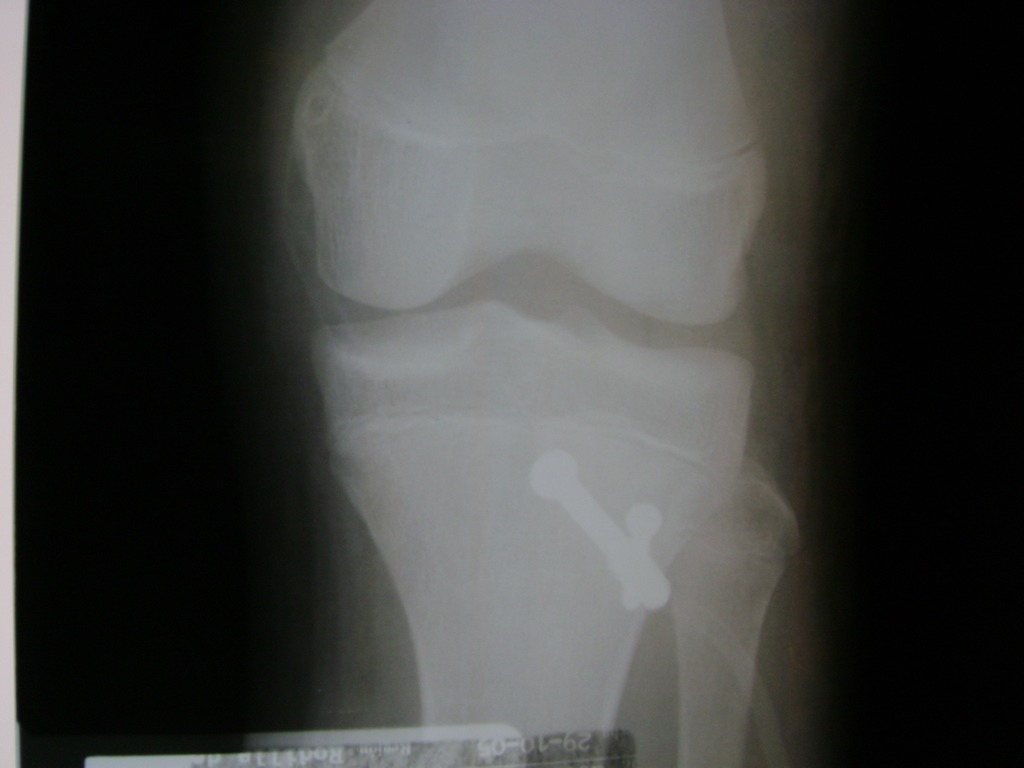

Cirugías de Húmero - Rodilla

La artroscopia de rodilla es un cirugía en el cual la estructura interna de la articulación es examinada ya sea para realizar un diagnostico o para realizar un tratamiento, este procedimiento se realiza utilizando un instrumento parecido a un pequeño tubo llamado artroscopio.